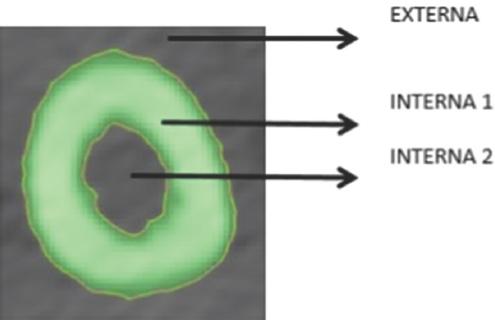

Los cortes tomográficos obtenidos se trabajaron en 3-matic (Materialise Inc., Leuven Bélgica) para la medición del diámetro y la recopilación de los datos. De las imágenes obtenidas por el software, se realizaron tres mediciones del canal medular: interna (diámetros de los vástagos), interna (diámetros de la corona) y externa (diámetro del implante), además de la longitud del húmero (Fig. 4).

Figura 4 Medición de los cortes tomográficos del húmero (longitud y diámetro), limpieza del canal medular de tomografías computadas para su medición (8 cm distal y 6 cm proximal). Creación de polilíneas, curvas y medición. Software: Mimics, 3-matic (Materialise Inc., Leuven Bélgica).